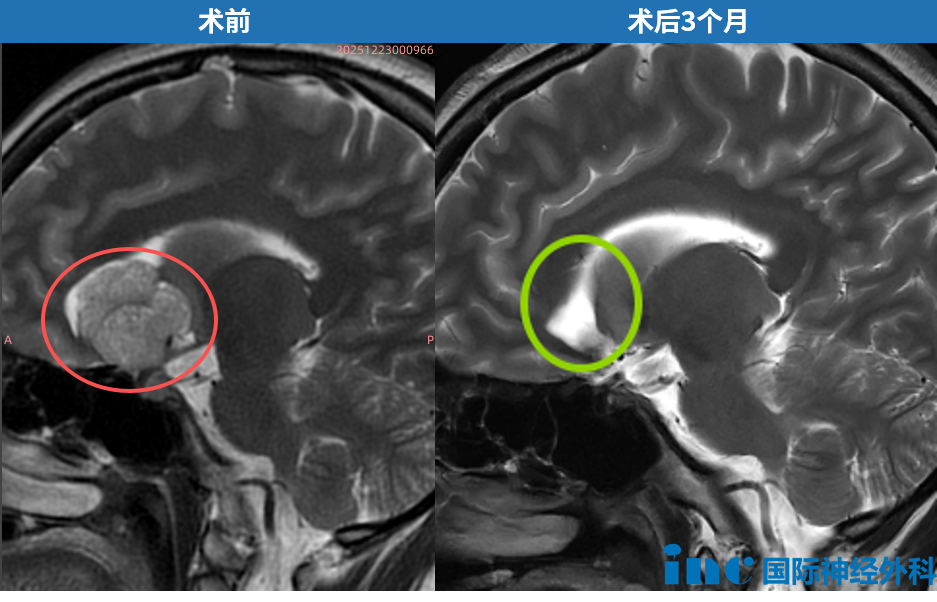

巴教授仔细查阅面前这位随访患者的术前术后影像资料,神情笃定:"你很幸运。同样是这种巨大垂体瘤,很多患者手术后往往难以维持完整的垂体功能,激素水平无法恢复正常,甚至可能永久丧失生育能力。而你的垂体组织得到了很好的保护,功能完全正常。"

再度与巴教授面对面,听到这样确切的评估,术后三个月的武女士和爱人脸上重新绽放出踏实而灿烂的笑容。谁能想到,就在数月前,年仅27岁、刚刚订婚不久的她,因一枚巨大的鞍区肿瘤,曾深陷"我完了"的绝望深渊。如今走出阴霾,她将这段经历如实分享,希望能为同样与病痛抗争的陌生人带去更多希望。

而她的肿瘤,恰恰就从这"命门"深处生长,并向额叶蔓延,侵犯了大脑前动脉。手术的难点与核心风险,正在于如何在彻底切除鞍内肿瘤的同时,完好无损地保全垂体与垂体柄。

这份笃定,在术后得到了完美的印证。三个月后的随访复查,带来了一连串好消息:激素水平正常,可以如常生活。朋友见了她都感叹:"你这跟没做手术一个样儿!"给朋友当伴娘、过年走亲访友、聚会吃饭,生活已全然回归正轨。内分泌科医生"激素几乎没有影响"的评价,更让她和爱人彻底放下了心。